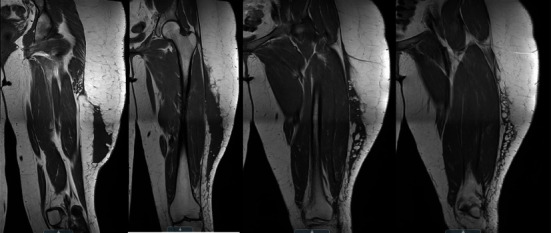

Morel-Lavallée lesions are serious internal degloving injuries associated with trauma. Its diagnosis and treatment can be challenging. We describe the surgical treatment of a case of a chronic Morel-Lavallée lesion in a pediatric patient who sustained an injury to her left thigh during an all-terrain vehicle accident more than a year ago.